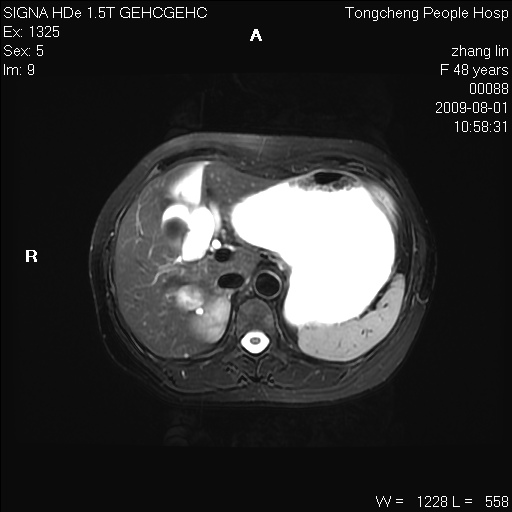

女,48岁。健康体检,彩超发现右肾占位性病变。平素健康。

临床诊断:右肾占位性病变,性质待定(囊肿?肿瘤?)。

上中腹部mr平扫+增强扫描,图像如下:

右肾上极见一类圆形病灶,t1wi呈等信号t2wi呈等高混杂信号,三期增强无强化,边界清---考虑囊肿出血。

同反相位均表现为等信号,病变无强化,考虑含蛋白的囊肿可能,弥散加权相或许有些帮助,

慢性胆囊炎